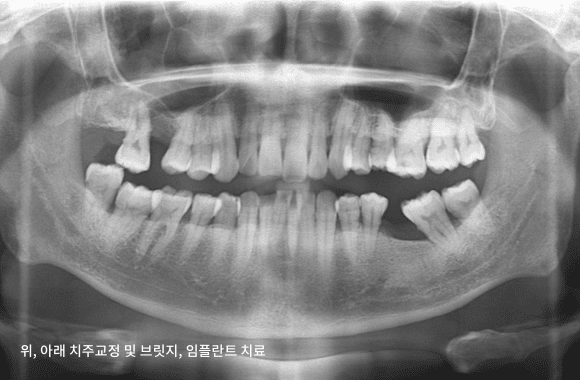

시니어 부분교정